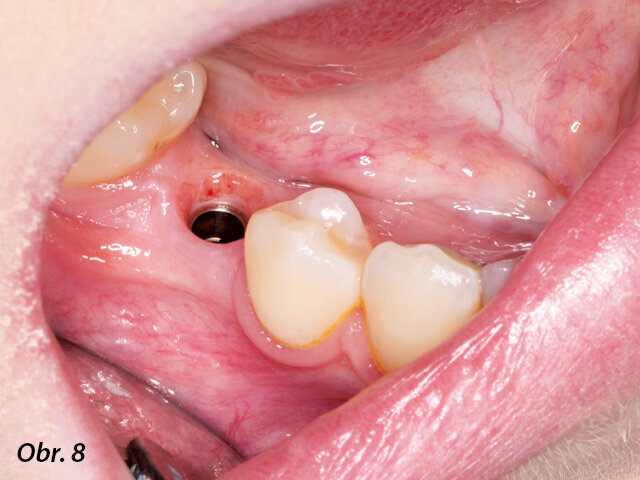

Na implantát byl po chirurgickém zákroku umístěn vhojovací abutment.

Po zavedení implantátu pomocí chirurgické šablony byl na implantát umístěn provizorní vhojovací abutment, který měl napomoci zhojení a vytvarování měkkých tkání do doby, kdy bude možné naplánovat definitivní náhradu.